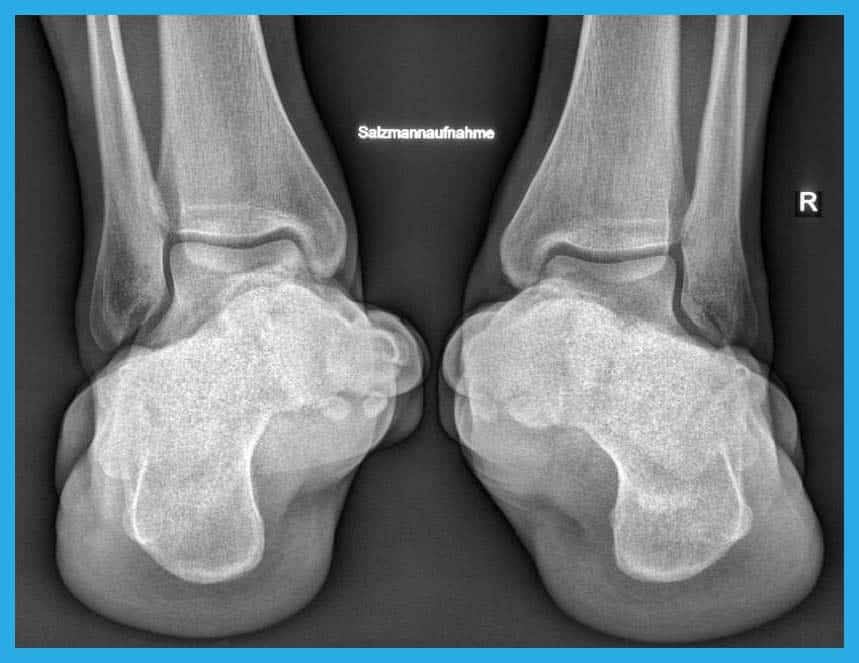

Left/Top: Illustration of flat feet before surgery.

Right/bottom: Image of flat feet after surgery with Shark Screw®.

The left/upper image shows auntreated flat feet before surgery. The right/bottom picture shows flat feet treated with Shark Screw® after surgery.